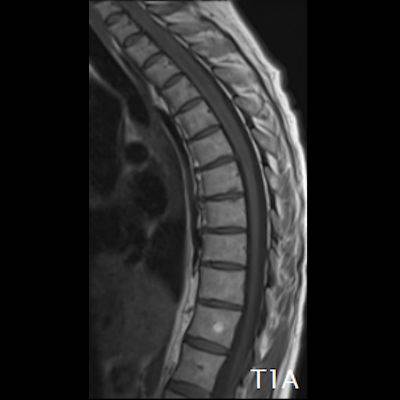

- (A) Torakal MRG’de sagital görüntülerde üst-orta torakal düzeyde T2A hiperintens (oklar), T1A izo-hipointens (ok) uzun segment ekspansil sinyal değişikliği izlenmekte olup sagital postkontrast T1A’da kontrast tutulumu mevcuttur (oklar). Bulgular longitudinal ekstensif transvers miyelit (LETM) ile uyumludur.

- Transvers miyelit sıklıkla santral gri cevheri etkileyen ve üç veya daha fazla vertebral gövde uzunluğunu etkilemektedir (LETM).

- Transvers kesitlerde, santral kordu tutma eğilimindedir.

- Omurilik atrofisi ve ekspansiyon/ödem MS’e göre daha fazla görülür.

- Kontrast madde enjeksiyonu sonrasında neredeyse tüm akut NMO lezyonları, yamalı, düzensiz veya periferik olarak kontrastlanma gösterir.